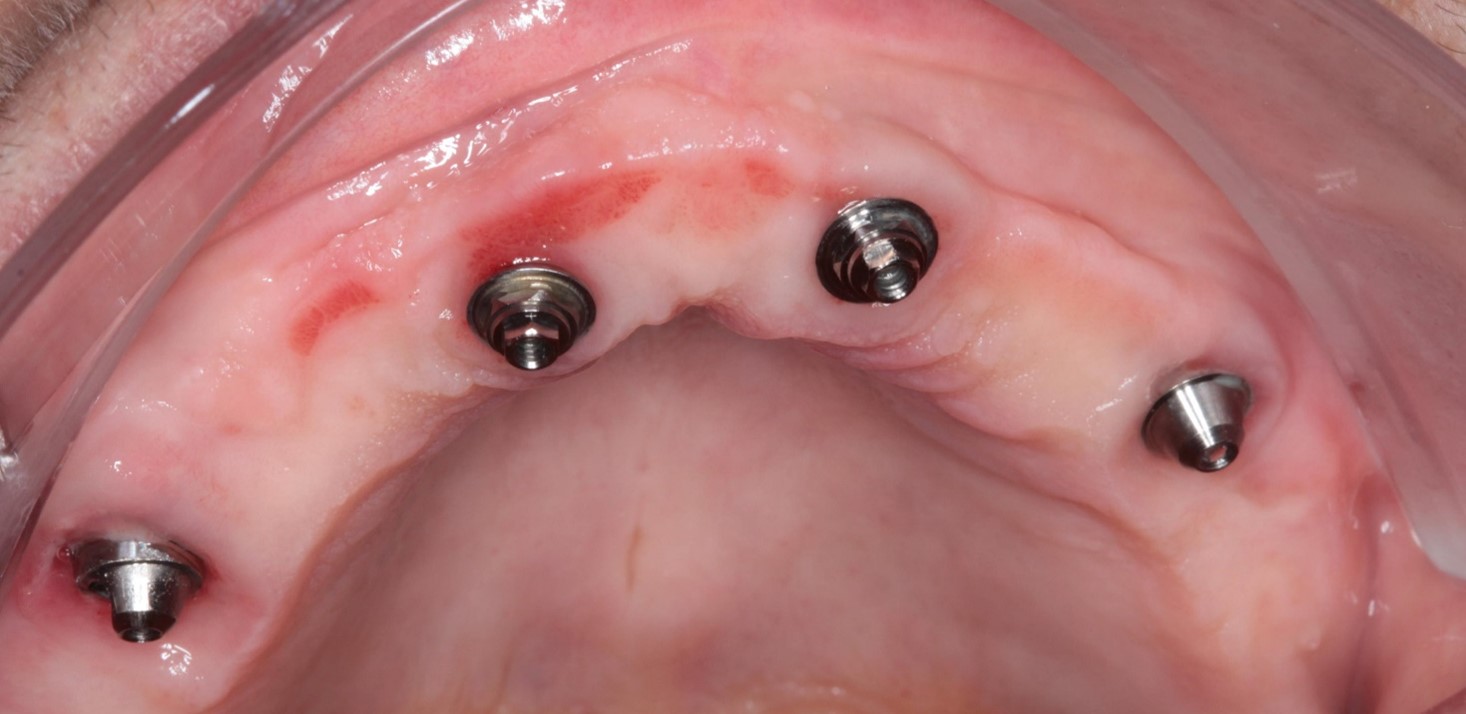

Fig. 1 e 2 – Vista oclusal

Todos os implantes atingiram um torque de 80 N, possibilitando a realização de carga imediata. Mini pilares retos com transmucoso de 2mm foram instalados nos implantes anteriores e mini pilares angulados de 30 graus com transmucoso de 3mm nos distais, corrigindo a ajuste dos implantes e sustentando o assentamento passivo da barra.

FIG. 11 – Aspecto do tecido mole após 17 meses da cirurgia.

FIG. 13a b c – Aspecto dos tecidos moles após 26 meses da cirurgia.